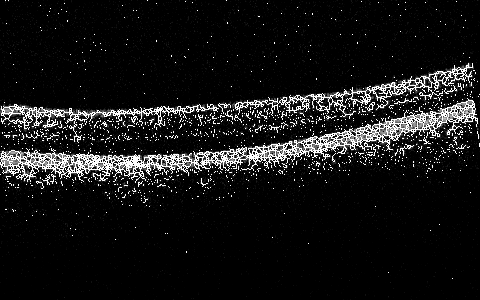

To preliminary tests of loading, basic manipulation, and dumping are successful, as per Figure 4 and Figure 4. These simply illustrate that the data are loaded and interpreted correctly from the provided data set in Section 0.3.2.

Refer to caption

Figure 3: Test of Loading Provided Data in PPM To Match Provided

Figure 4: Test of Rudimentary Processing via Threshold

Some experiments are in place to test the data processing, the framework’s API operation, and some actual algorithms. That includes loading of the .txt data and its subsequent dump back as an image work (see Figure 3) as well as testing the data structure by rudimentary processing of the loaded data’s pixels by simply discarding values below certain intensity threshold and amplifying the remaining ones to the max as a very basic test (see Figure 4) to ensure the given data understanding is correct via Binarizer.